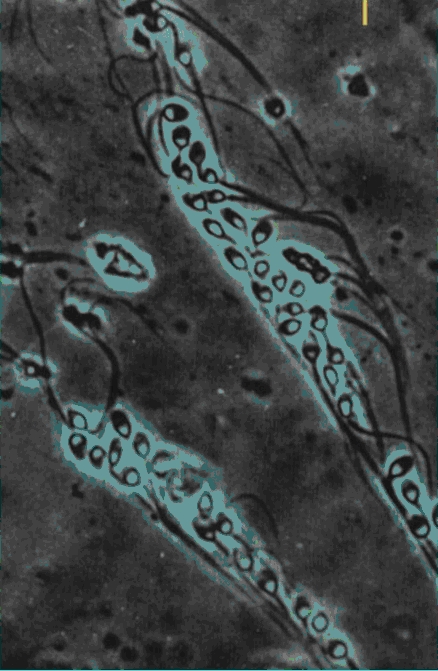

- ASSISTED HATCHING: in certi casi di fallimenti ripetuti di fecondazione assistita, il mancato impianto dei pre-embrioni può derivare dalla loro incapacità di fuoriuscire dalla zona pellucida, involucro in cui sono racchiusi nelle prime fasi di sviluppo. Tecnicamente è possibile tramite il micromanipolatore, sotto visione microscopica, interrompere in vari modi la continuità della zona pellucida facilitando l’impianto dell’embrione nell’endometrio. È di osservazione relativamente recente che, con tale metodica, è possibile ottenere un significativo aumento nei tassi di impianto del pre-embrione.

| rottura della zona pellucida e liberazione della blastocisti |